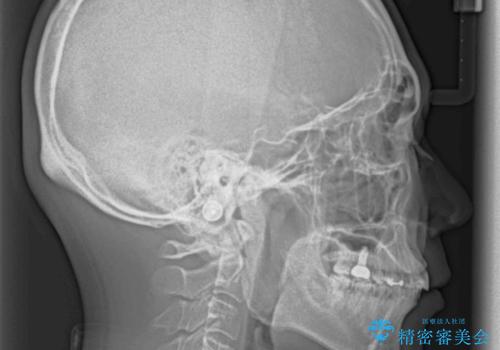

- 深い咬み合わせと前歯のデコボコ、奥歯の欠損を気にして来院された患者様です。

歯列矯正はインビザラインを使用し、矯正治療中の適切な時期に奥歯の欠損部位にインプラントを埋入することとしました。